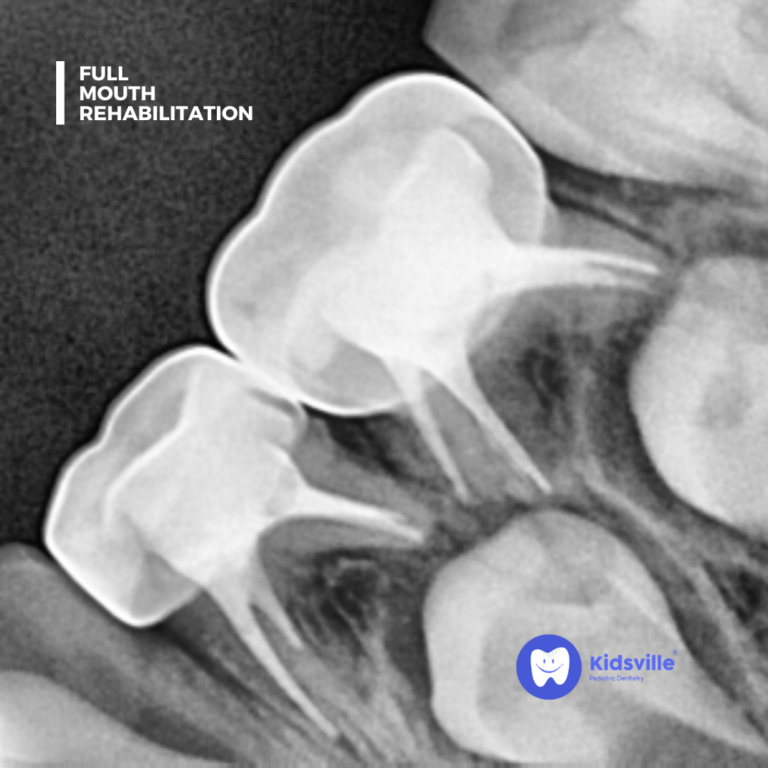

A thorough examination and diagnostic tests (such as digital X-rays) to assess the condition of all teeth and gums.

Fillings and Crowns

Restoring teeth that have been damaged by decay.

Root Canal Treatment (RCT)

For saving severely decayed or infected teeth.